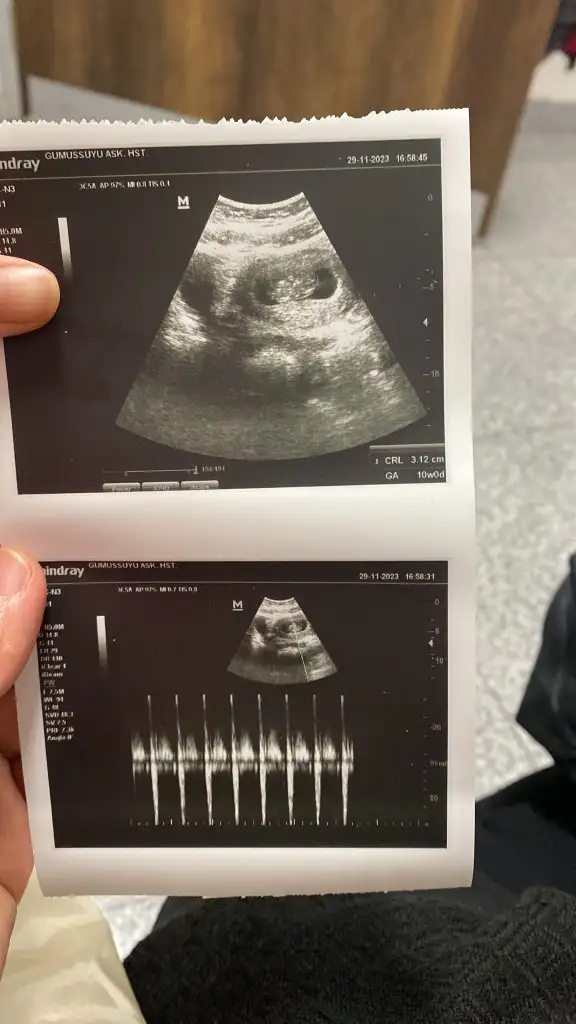

Merhaba cinsiyeti nedir bebeğinizinmerhaba keseden cinsiyet tahmini yapılıyormus 10. Hafta ultrason görüntümüz tahmini olan varmi

9+4 hafta karından ultrason tahmini olan var mımerhaba keseden cinsiyet tahmini yapılıyormus 10. Hafta ultrason görüntümüz tahmini olan varmi

Bende gondersem yorumlarmisinizHayırlı olsun öncelikle , bu ilk ultrason görüntüsü ise erkek bebek tutunma şekligönlünüzden geçen sağlıkla gelsin

Hayırlı olsun öncelikle , bu ilk ultrason görüntüsü ise erkek bebek tutunma şekligönlünüzden geçen sağlıkla gelsin